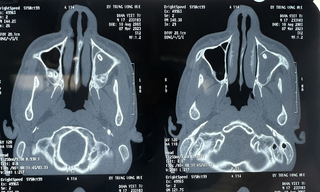

từ khóa: #đóng lỗ thông xoang hàm